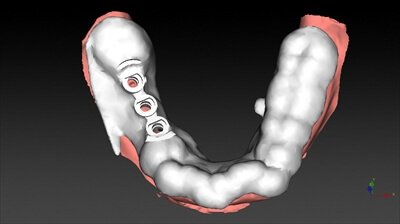

⑤別の角度からも詳細に確認します。

⑥完成したノーベル・ガイドです。